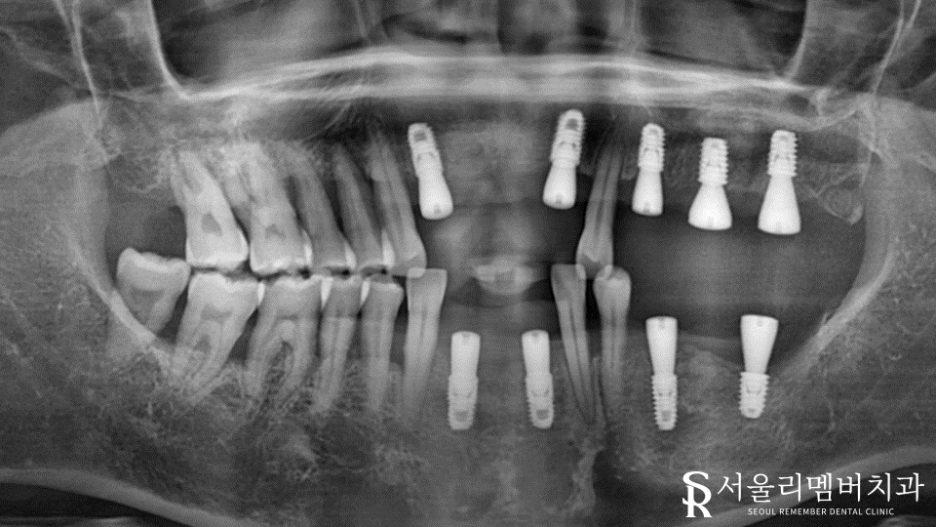

봉천동 치과 에서는 위 진단 내용을 토대로 아래와 같이 계획을 세웠습니다.

발치가 필요한 곳들을 깨끗하게 뽑아준 뒤 픽스처 식립 진행했습니다.

원래 잇몸질환이 심한 분이어서 잘 심어질 수 있을까 걱정이 되었는데요.

올바른 계획과 정확한 식립을 통해 튼튼한 고정력을 얻을 수 있었습니다.